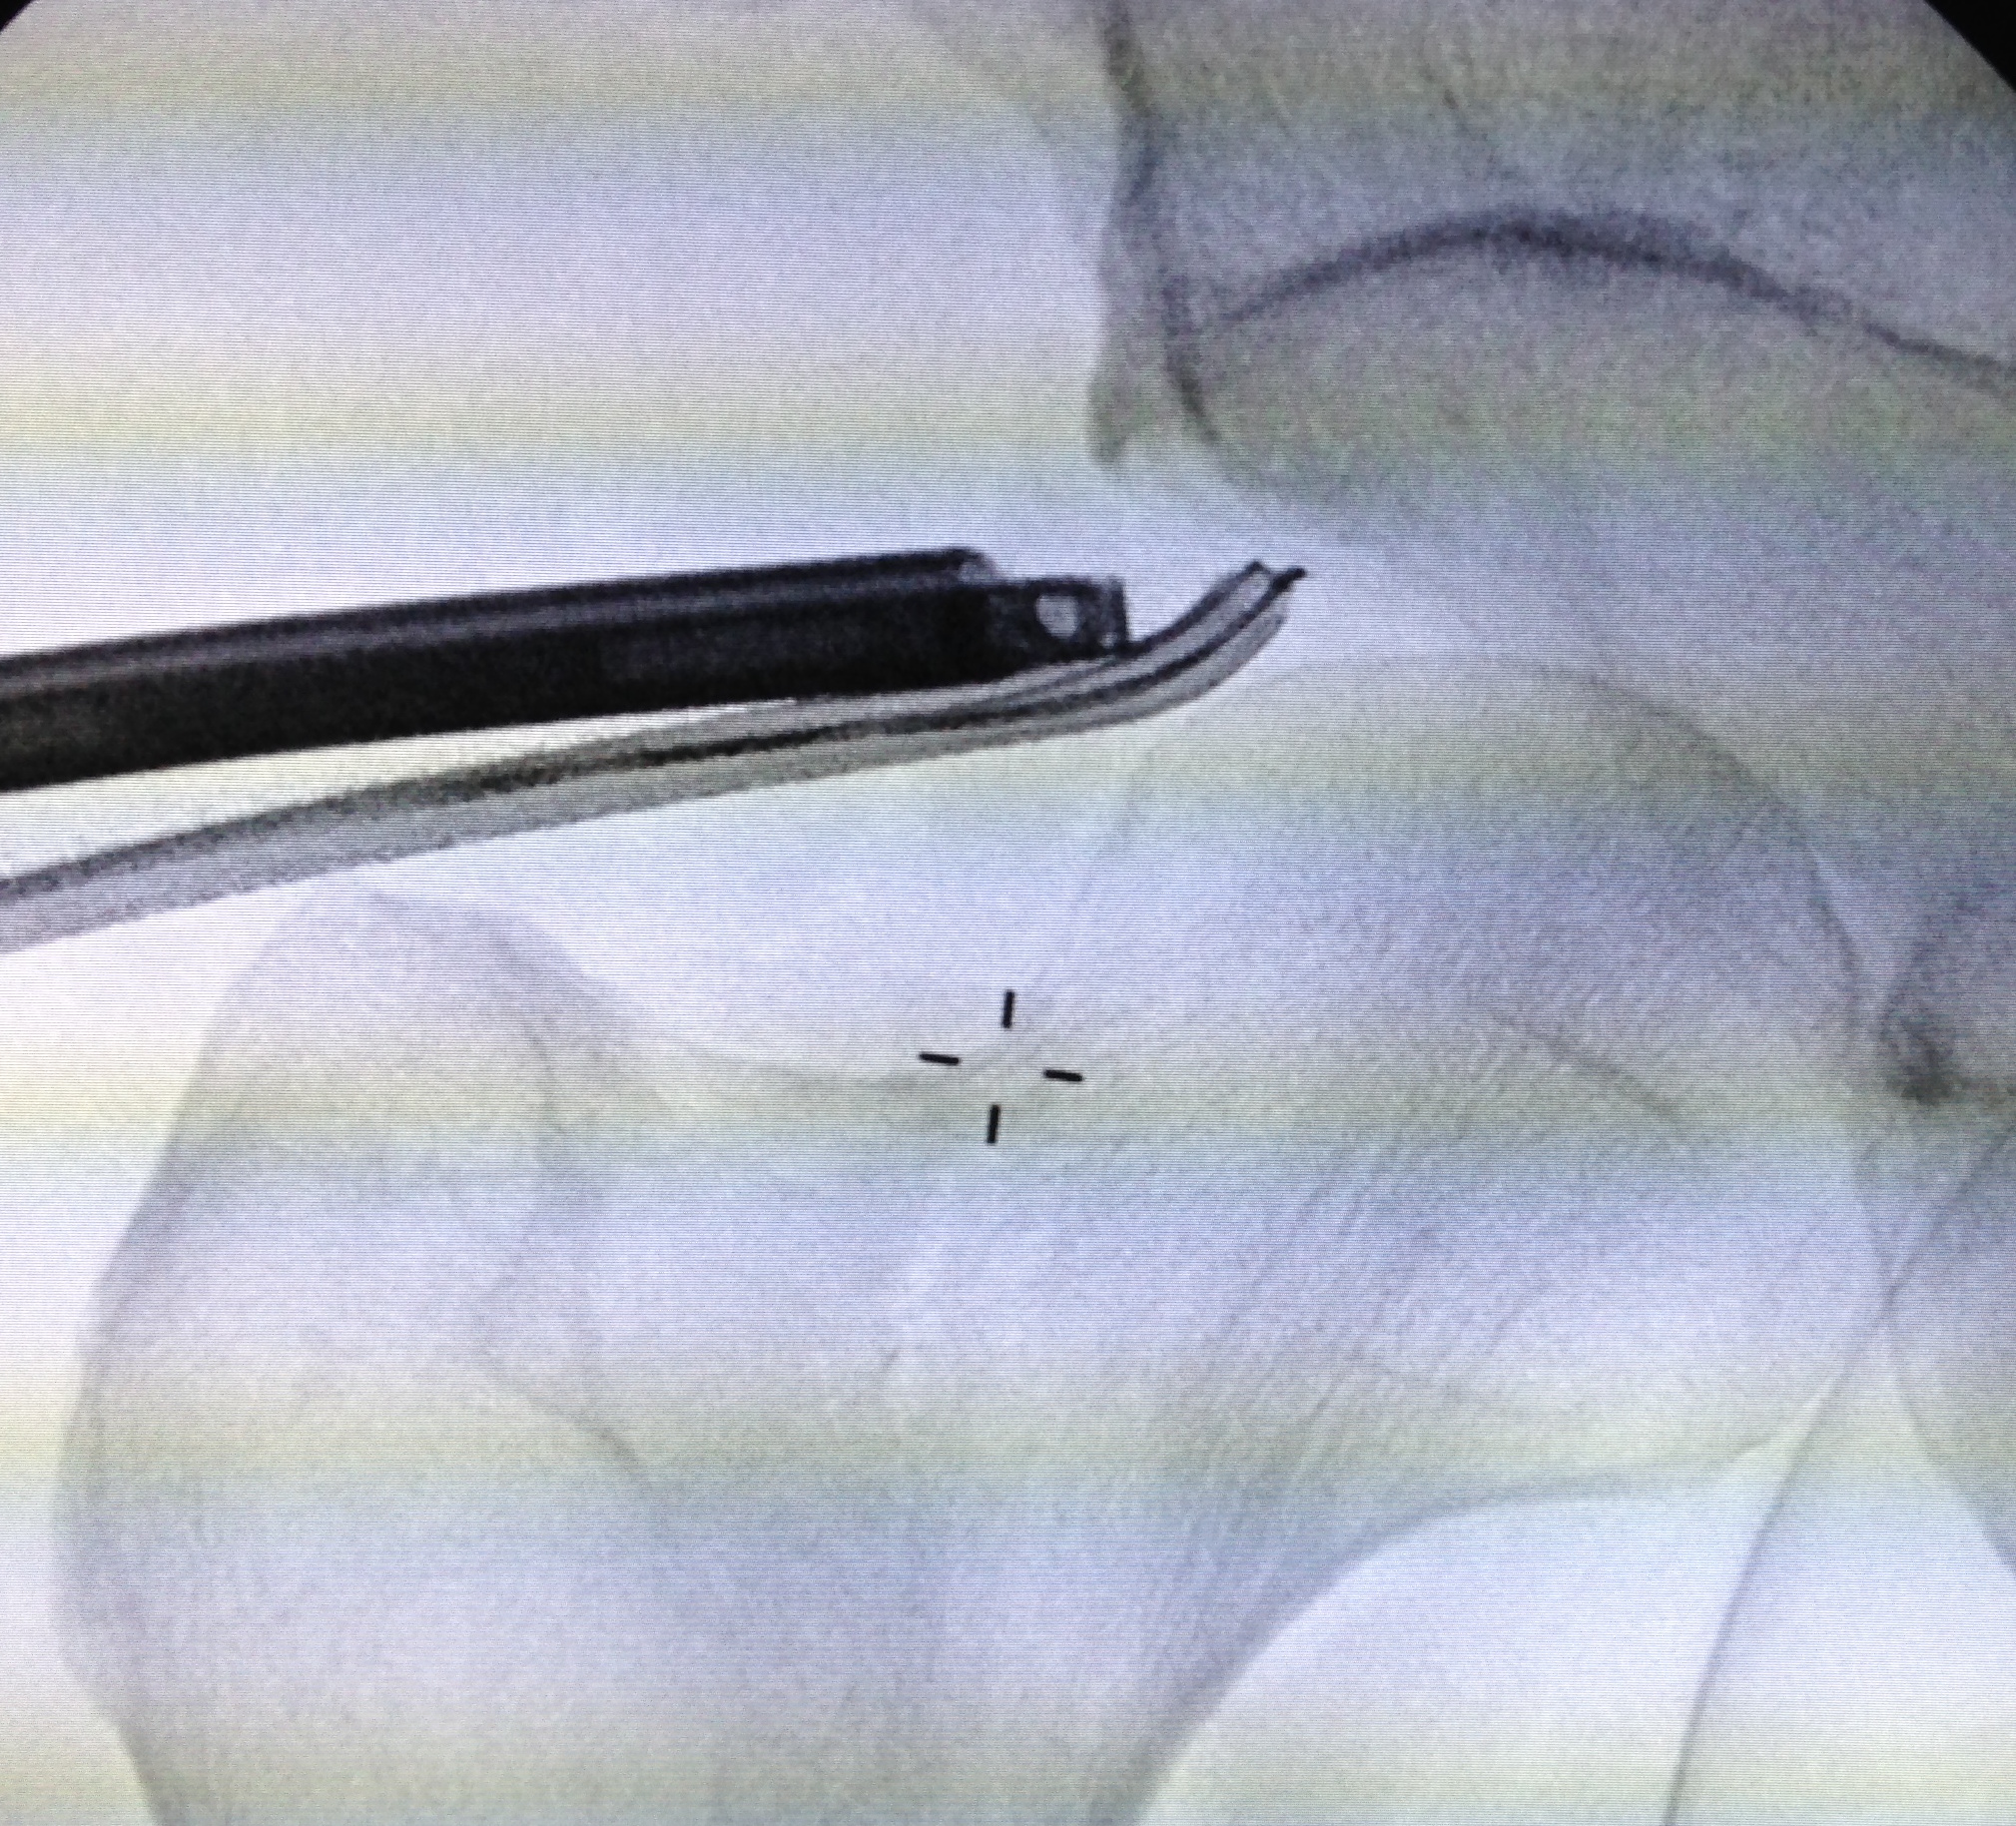

PALA

Insertion of PALA under image intensifier